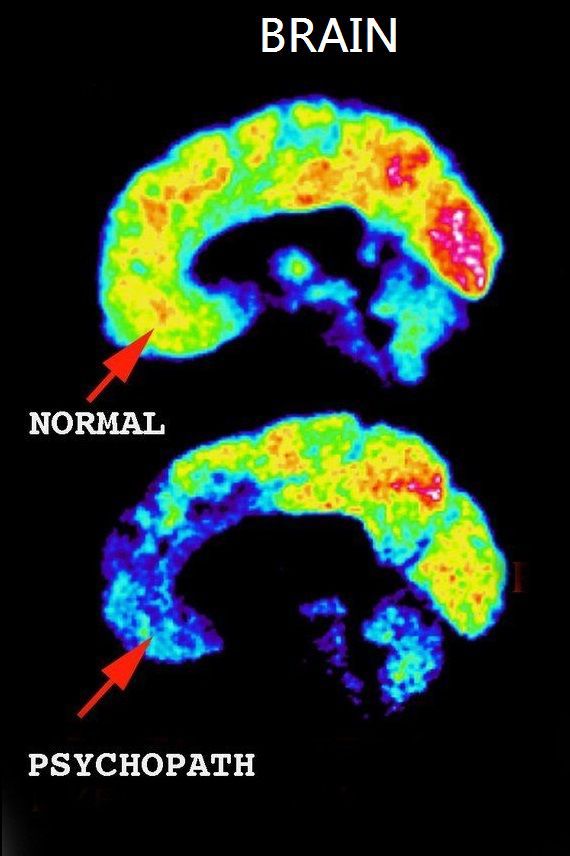

“The last scan in the pile was strikingly odd. In fact it looked exactly like the most abnormal of the scans I had just been writing about, suggesting that the poor individual it belonged to was a psychopath—or at least shared an uncomfortable amount of traits with one....When I found out who the scan belonged to, I had to believe there was a mistake....But there had been no mistake. The scan was mine.” For the first fifty-eight years of his life James Fallon was by all ...